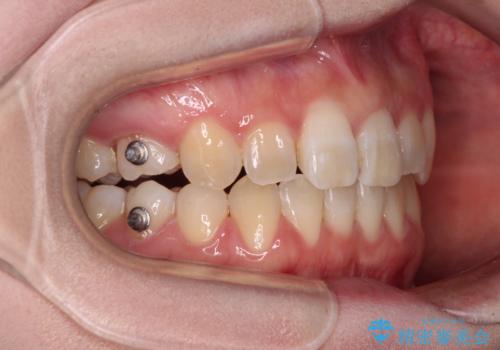

- 前歯のデコボコと強い咬みしめを気にして来院された患者様です。

インビザラインを用いて、前歯の叢生を解消するとともに、ディープバイトを改善していくこととしました。

上顎に乳歯が左右1本ずつ残っていたため、若干咬み合わせに不具合が残りましたが、強い咬合力の原因であったディープバイトをしっかりと改善することができました。